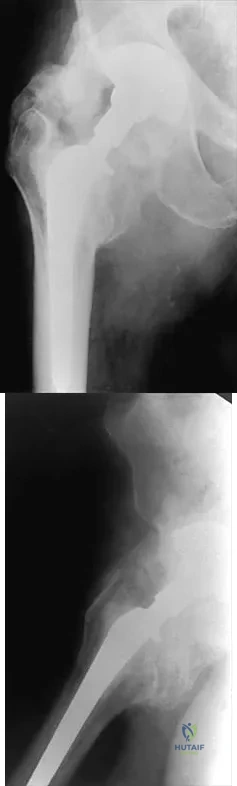

Figures 22a and 22b show the radiographs of a patient who reports stiffness of the hip and associated pain. Management should consist of

Explanation